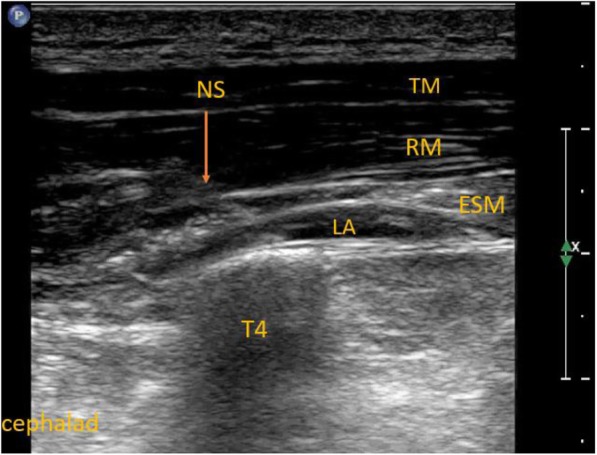

In the ESP group, ultrasound-guided ESP block at the fourth thoracic level was performed before the surgery and induction of general anesthesia with Ropivacaine (0.375%; Ropimol, Molteni, Italy, 0.2 mL/kg) as described in our previous study (Fig. 1) [13]. The maximum dosage of ropivacaine could not exceed 20 mL in this group. In the PECS + ESP group, in addition to ESP block, ultrasound-guided PECS blocks type I and II were performed. Local anesthetic (6–8 ml) was deposited in the fascial plane between the pectoralis major and minor muscles (PECS I, Fig. 2); 12–14 ml was deposited between the pectoralis minor and serratus anterior muscles (PECS II, Fig. 3). The total dose of local anesthetic could not exceed 40 mL (150 mg of ropivacaine) in this group.

Fig. 1.

Erector spinae plane block. ESM – erector spinae muscle, LA – local anesthetic, NS- needle shaft, RM- rhomboid muscle, T4 – the transverse process of the fourth thoracic vertebra, TM – trapezius muscle